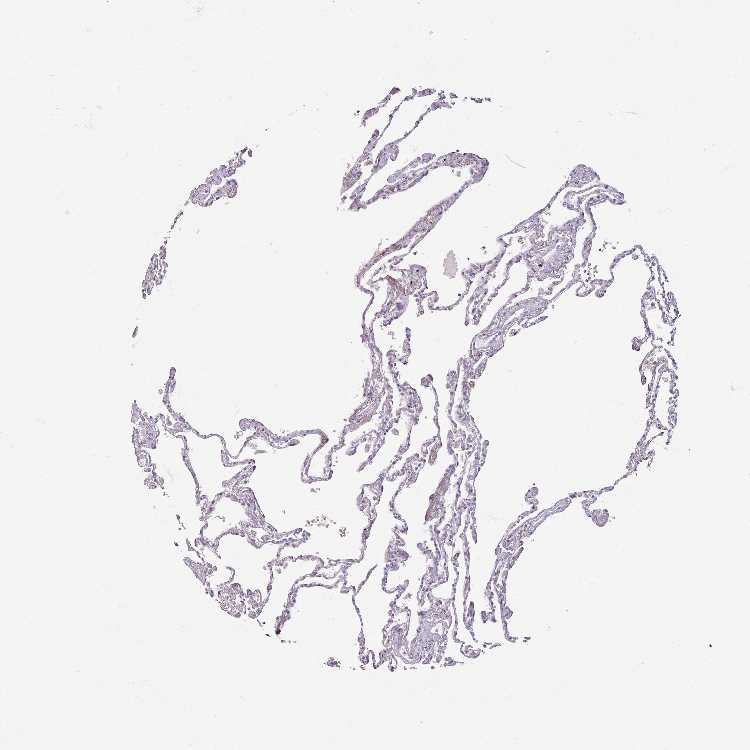

LUNG - Antibody stainingi

Antibody staining in the annotated cell types in the current human tissue is reported as not detected, low, medium, or high, based on conventional immunohistochemistry profiling in selected tissues. This score is based on the combination of the staining intensity and fraction of stained cells.

Each image is clickable and will lead to virtual microscopy that enables deeper exploration of all samples and also displays staining intensity scores, fraction scores and subcellular localization as well as patient and tissue information for each sample.

Antibody HPA000536Antibody CAB056152Antibody CAB056153

Alveolar cells Not detectedNot detectedNot detected

Macrophages Not detectedNot detectedNot detected